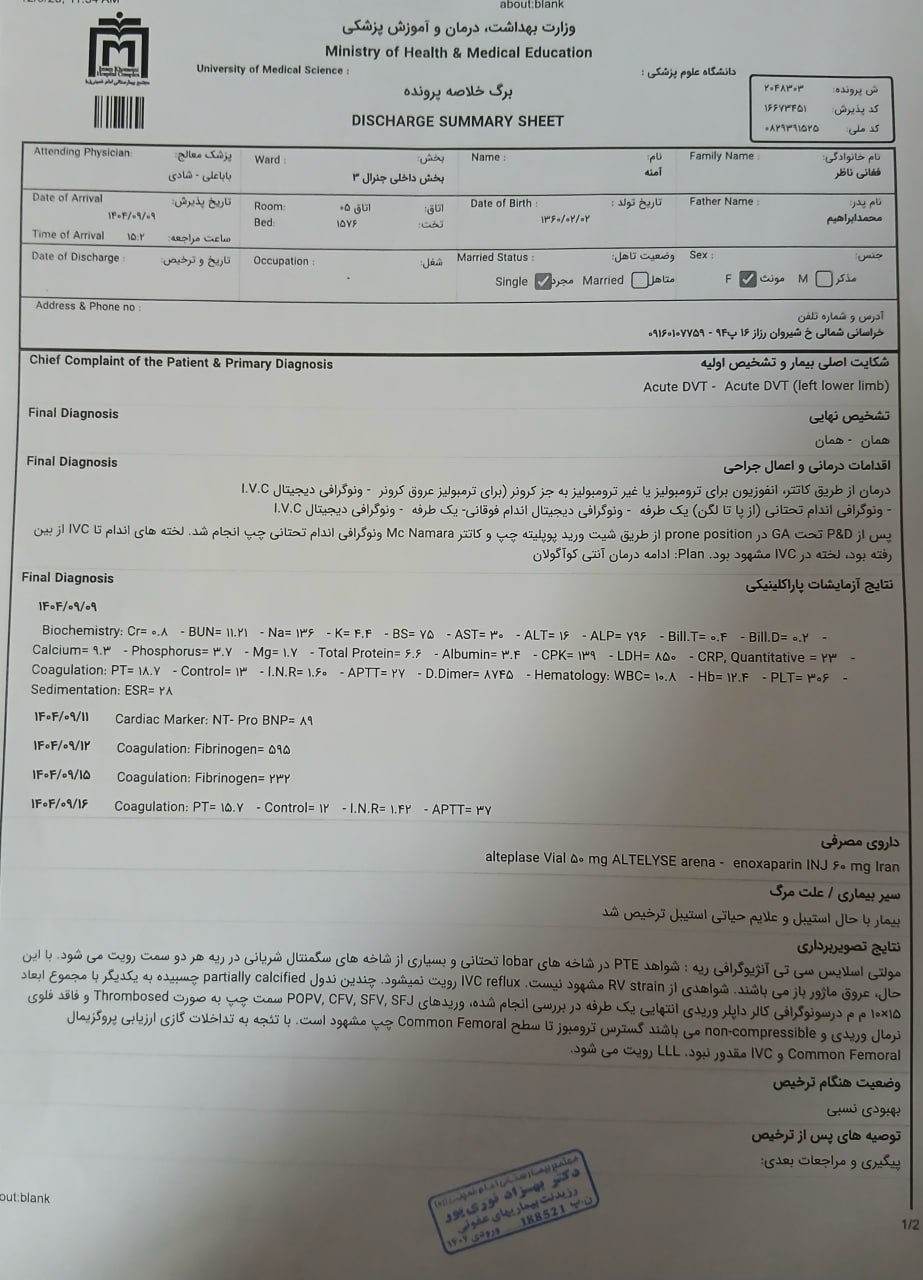

بیمار، در تاریخ 18.9 ، به دلیل تورم اندام تحتانی چپ از سرح ران و درد شدید سراسر اندام تحتانی چپ به همراه اختلاف سایز اندام ها در تهران بستری شده است. در بررسیها جهت بیمار تشخیص ترومبوز ورید عمقی (DVT) اندام تحتانی چپ مطرح شده است و تحت درمان DVT قرار گرفته است.

DVT اندام تحتانی چپ یک ماه پیش

مراجعه کرده است. پس از بررسی های انجام شده در MRI انجام شده توده با درگیری مفصل ساکروایلیاک چپ و DVT؛ ابتدا تحت درمان DVT قرار گرفته است و سپس جهت پیگیری تومور رویت شده تحت بیوپسی قرار گرفته است و با تشخیص کندروسارکوما به این مرکز مراجعه کرده است و تحت کموتراپی و رادیوتراپی قرار گرفته و سایز تومور کاهش یافته است.